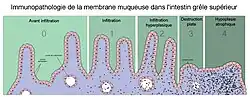

À la phase active de la maladie, avant le diagnostic et donc l'instauration d'un régime excluant le gluten, la majorité des malades ont une atrophie totale ou subtotale des villosités (disparition de ces dernières) au niveau de la paroi intestinale avec une nette augmentation du nombre de lymphocytes dans l'épithélium de cette dernière.

Cette atrophie est prédominante au niveau de l'intestin grêle proximal mais peut, quand l'atteinte est importante, être visible sur l'ensemble de l'intestin grêle. Elle conduit alors à un syndrome de malabsorption plus ou moins total avec notamment une malabsorption de la vitamine B12 au niveau du grêle distal. Le taux sanguin de cette dernière est alors très abaissé, provoquant une macrocytose.

Elle met en évidence une atrophie villositaire associée à une augmentation des lymphocytes intraépithéliaux, une hypertrophie des cryptes et une infiltration plasmolymphocytaire du chorion. Ces lésions sont évaluées selon la classification de Marsh, allant de I (simple augmentation isolée des lymphocytes intraépithéliaux) à IIIc (atrophie villositaire sévère)[53].